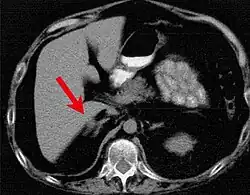

Rozrost mikroguzkowy nadnerczy (pierwotny pigmentowany rozrost drobnoguzkowy nadnerczy, dysplazja kory nadnerczy, łac. hyperplasia (dysplasia) micronodularis pigmentosa corticis glandularum suprarenalium, ang. primary pigmented nodular adrenocortical dysplasia, PPNAD) – rzadka choroba kory nadnerczy, występująca sporadycznie lub dziedzicznie. Obok rozrostu nadnerczy u chorych mogą występować śluzaki i plamista pigmentacja skóry. Dziedziczny rozrost mikroguzkowy nadnerczy znany jest także jako zespół Carneya od nazwiska amerykańskiego patologa J. Aidana Carneya, który opisał go jako pierwszy w artykule na łamach New England Journal of Medicine. Należy rozróżnić pierwotny pigmentowany rozrost drobnoguzkowy nadnerczy od triady Carneya (zwanej też kompleksem albo zespołem), opisanej przez tego samego badacza w 1983 roku, na którą składają się mięsak podścieliskowy żołądka, chrzęstniak płuca i pozanadnerczowy przyzwojak[2].